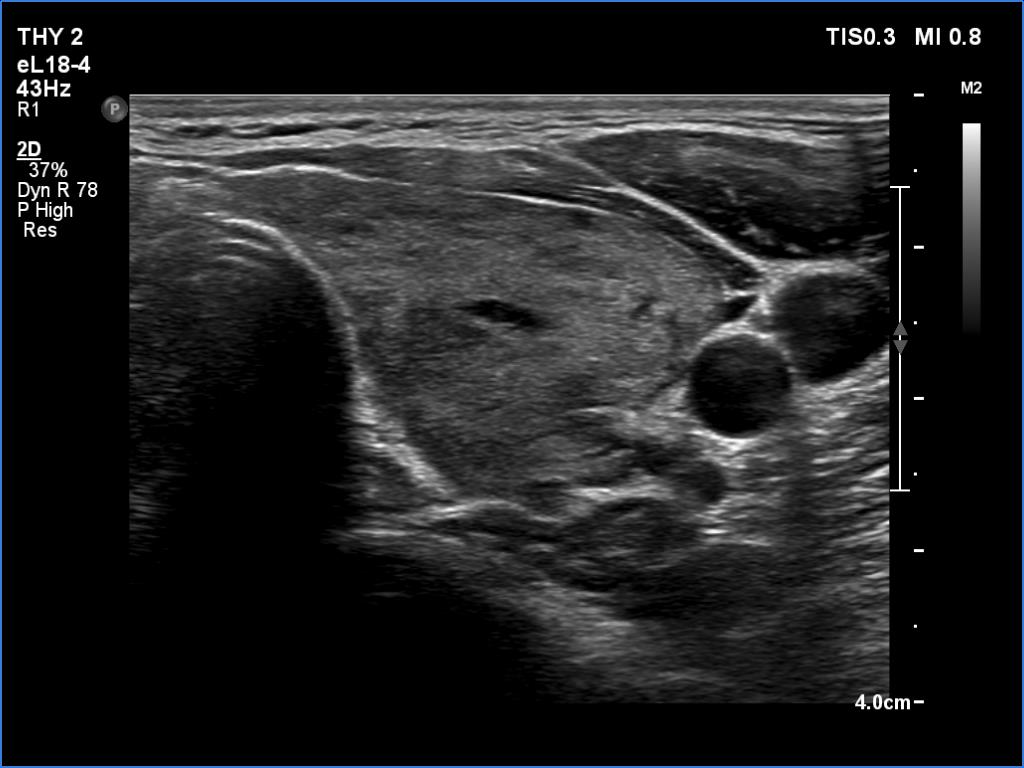

Left lobe, transverse scan

Left lobe, longitudinal scan